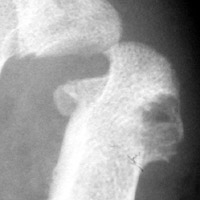

Gout: Erosions 1st MTP joint with preservation of joint space

+ ++